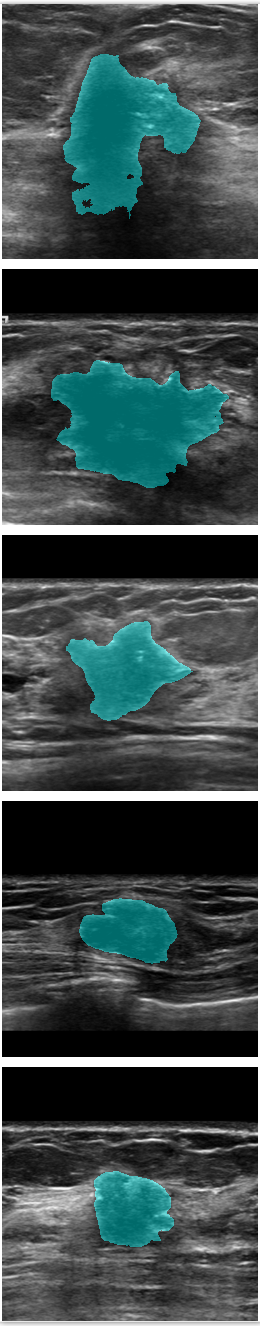

Refer to caption

Figure 7: Comparison of SPCGAN and other segmentation methods of malignant lesions.(a) shows original image of malignant lesions, (b) shows the manual annotation, (c) shows the result of SPCGAN ,(d), (e) and (f) show results from FCN(ResNet), Mask R-CNN and the level set method.

The examples given in Fig.7 correspond to the segmentation results of our SPCGAN, FCN(ResNet), Mask R-CNN and the level set method from malignant lesions. The FCN(ResNet) tends to oversegment the cancer when there is posterior shadowing, especially for the lesion in the first row. SPCGAN shows relatively more robust performance compared to FCN(ResNet), Mask R-CNN and the level set method.